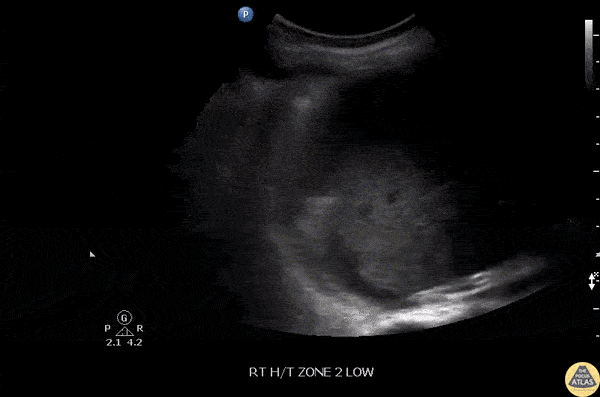

Small right anechoic parapneumonic effusion. Note B-lines seen at lung base. Curvilinear probe used. More commonly seen in bacterial pneumonia. Image courtesy of Robert Jones DO, FACEP @RJonesSonoEM Director, Emergency Ultrasound; MetroHealth Medical Center; Professor, Case Western Reserve Medical School, Cleveland, OH View his original post here